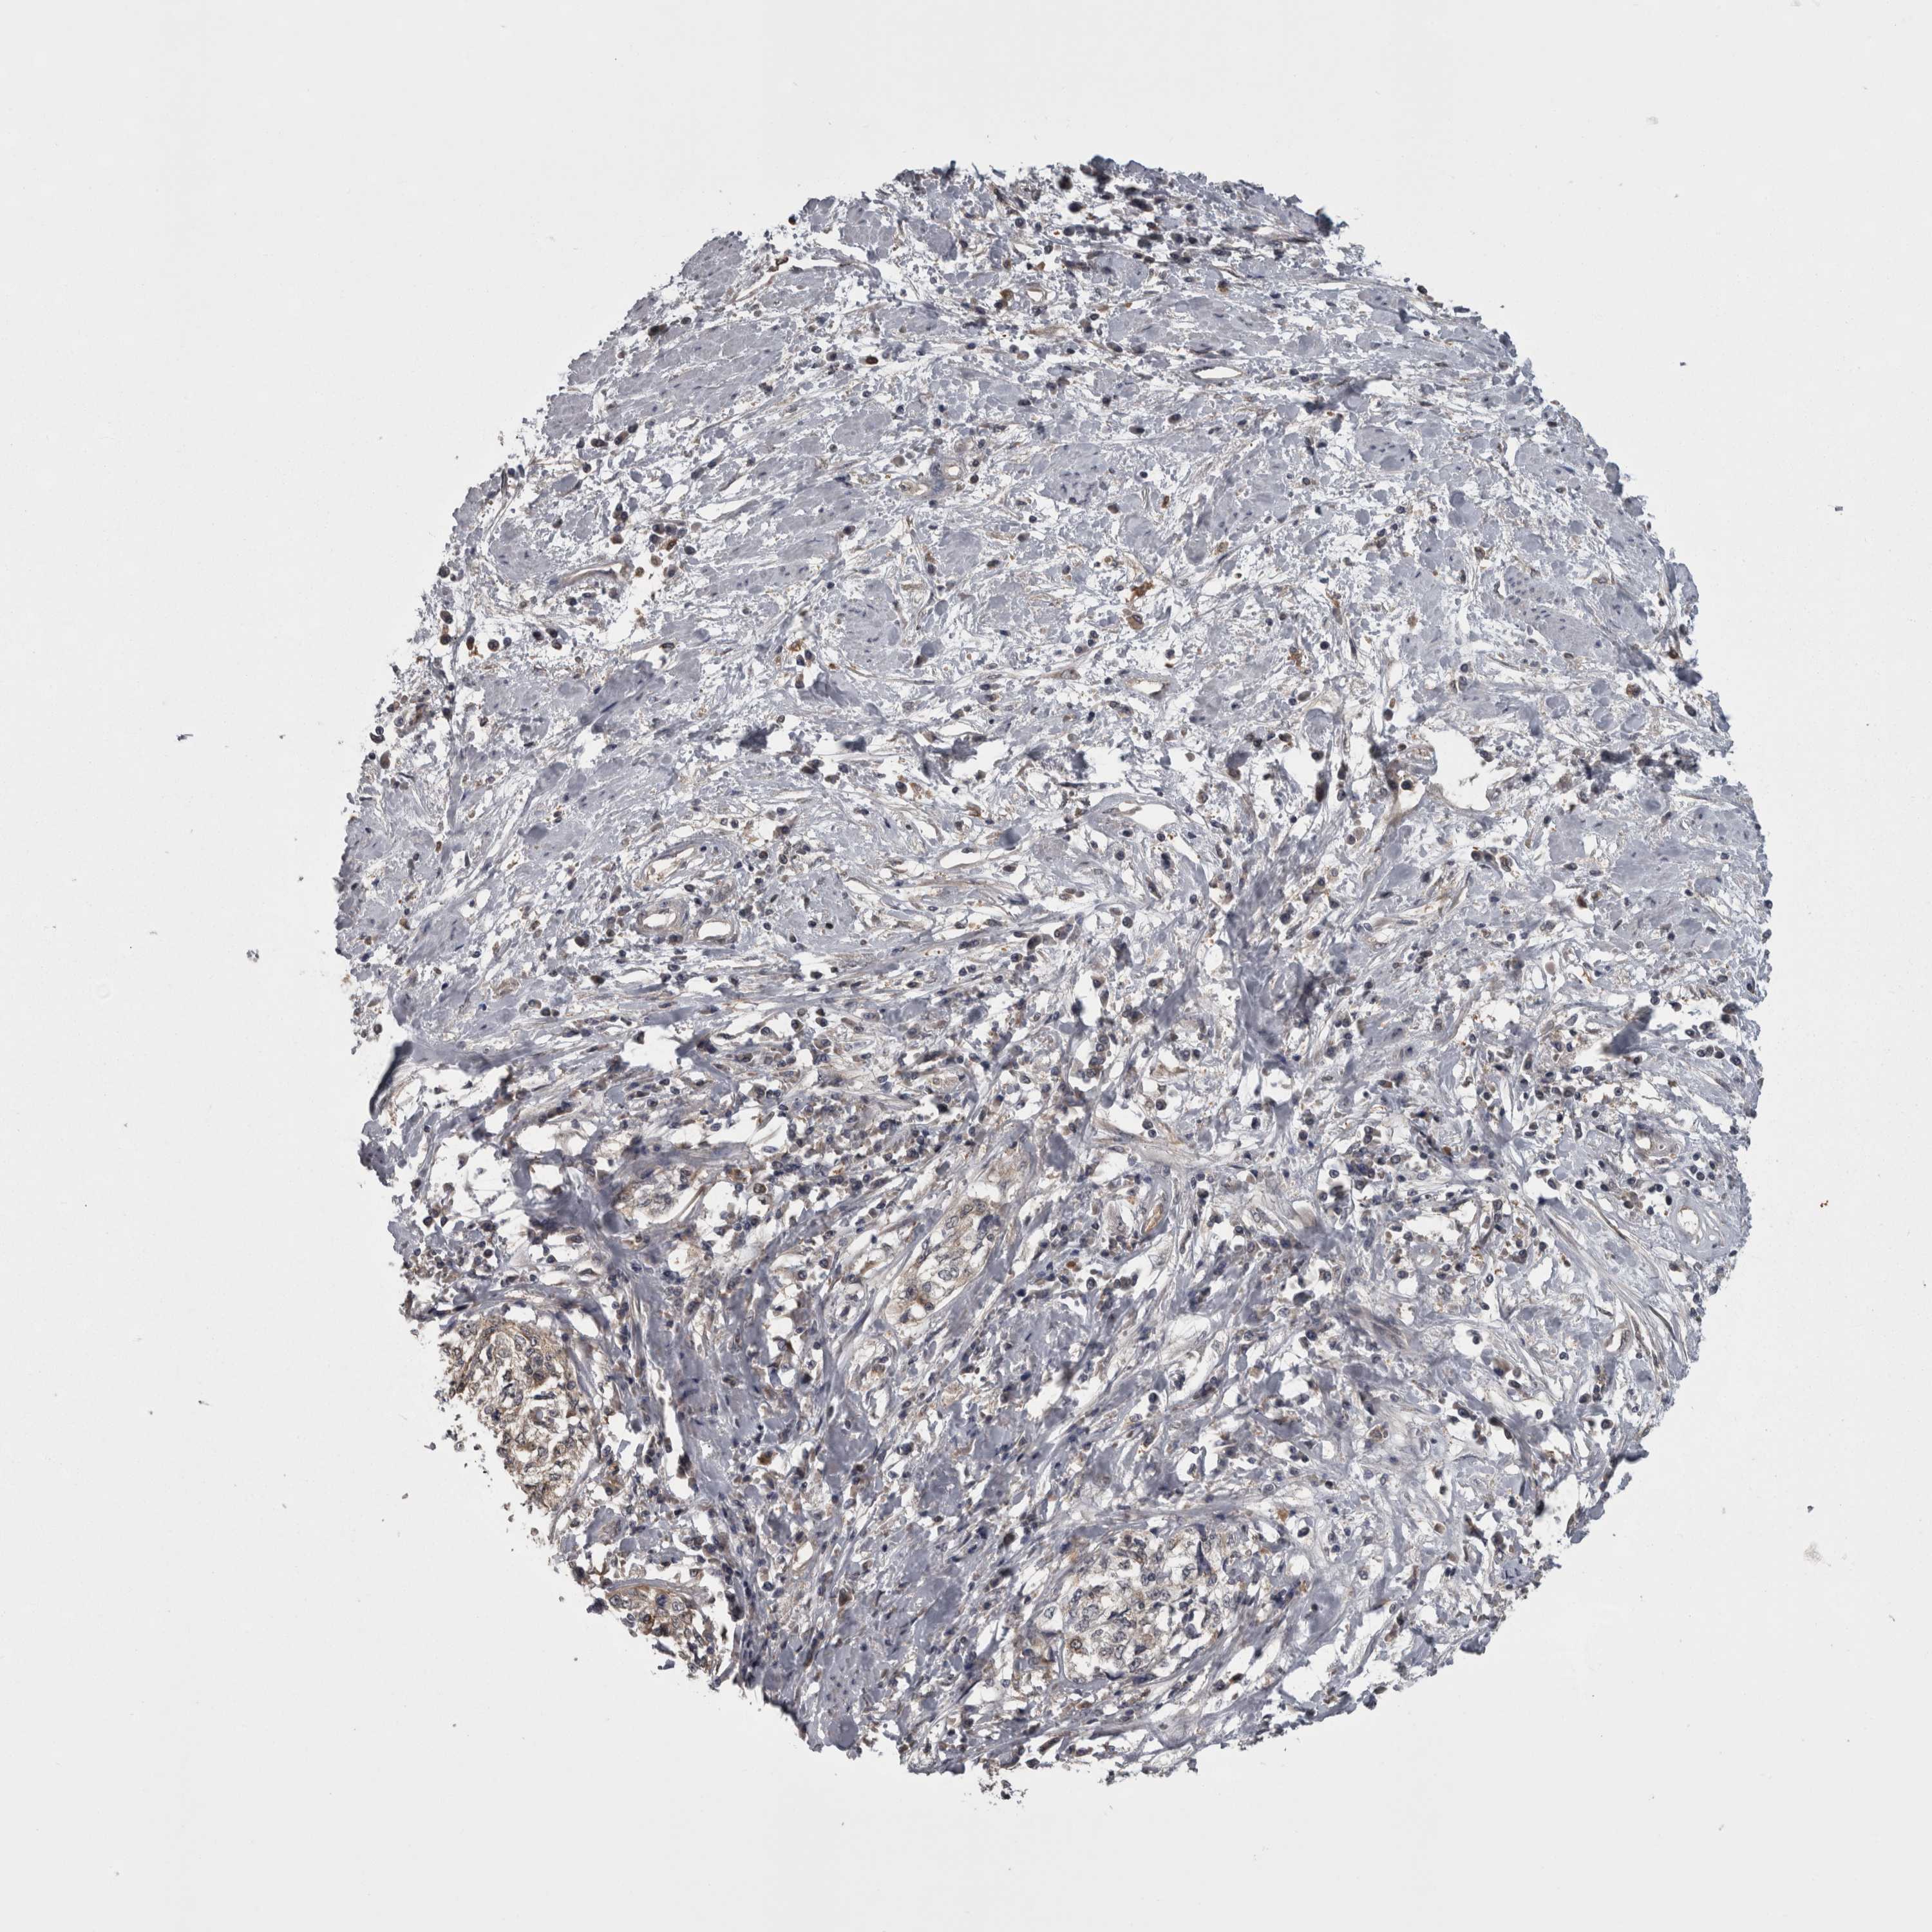

CERVICAL CANCER - Protein expressioni

A mouse-over function shows sample information and annotation data. Click on an image to view it in a full screen mode. Samples can be filtered based on level of antibody staining by selecting one or several of the following categories: high, medium, low and not detected. The assay and annotation is described here.

Note that samples used for immunohistochemistry by the Human Protein Atlas do not correspond to samples in the TCGA dataset.

Antibody stainingi

Antibody staining in the annotated cell types in the current human tissue is reported as not detected, low, medium, or high, based on conventional immunohistochemistry profiling in selected tissues. This score is based on the combination of the staining intensity and fraction of stained cells.

Each image is clickable and will lead to virtual microscopy that enables deeper exploration of all samples and also displays staining intensity scores, fraction scores and subcellular localization as well as patient and tissue information for each sample.

Antibody HPA026681

Staining

High

Medium

Low

Not detected

Intensity

Strong

Moderate

Weak

Negative

Quantity

>75%

75%-25%

<25%

None

Location

Nuclear

Cytoplasmic/membranous

Cytoplasmic/membranous,nuclear

Squamous cell carcinoma, NOS

Adenocarcinoma, NOS